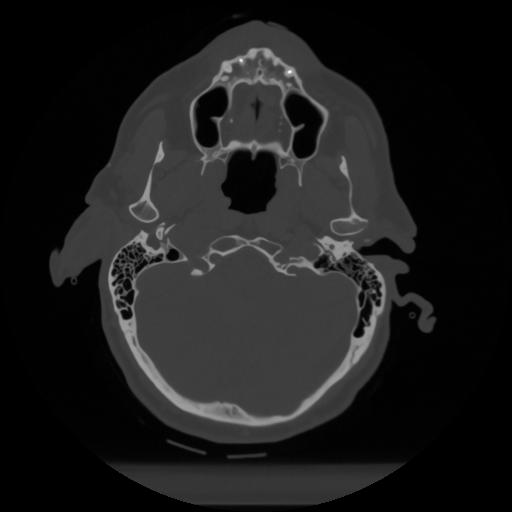

12 P.BLANDAS,,Vol,0.5,P.BLANDAS,,